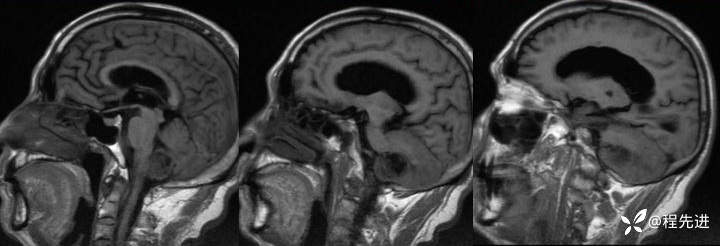

【患者信息】:男,66岁

【现病史及既往史】:头痛半年,行走不稳3个月

T1:

img